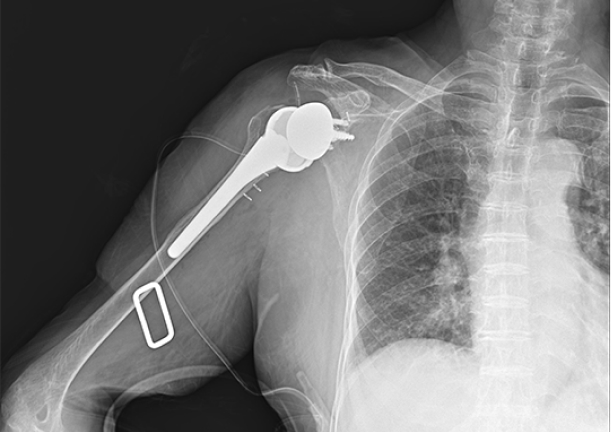

어깨를 들어올리기 훨씬 쉬운 역방향 인공관절

인공관절 수술은 매우 난이도가 높은 수술로 알려져 있습니다.

수술의 정확한 명칭은 어깨인공관절 치환술 (Shoulder replacement) 로 날아라정형외과에서는 최신 기술인

역방향 인공관절 치환술을(Reverse Total Shoulder replacement) 진행하고 있습니다.